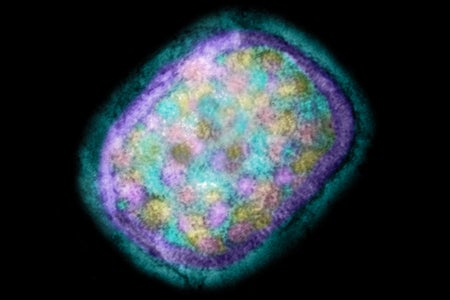

Mpox Explained: Transmission, Symptoms, Vaccines and Treatment

Frequently asked questions about how mpox spreads, who’s most at risk, and what vaccines and treatments are available